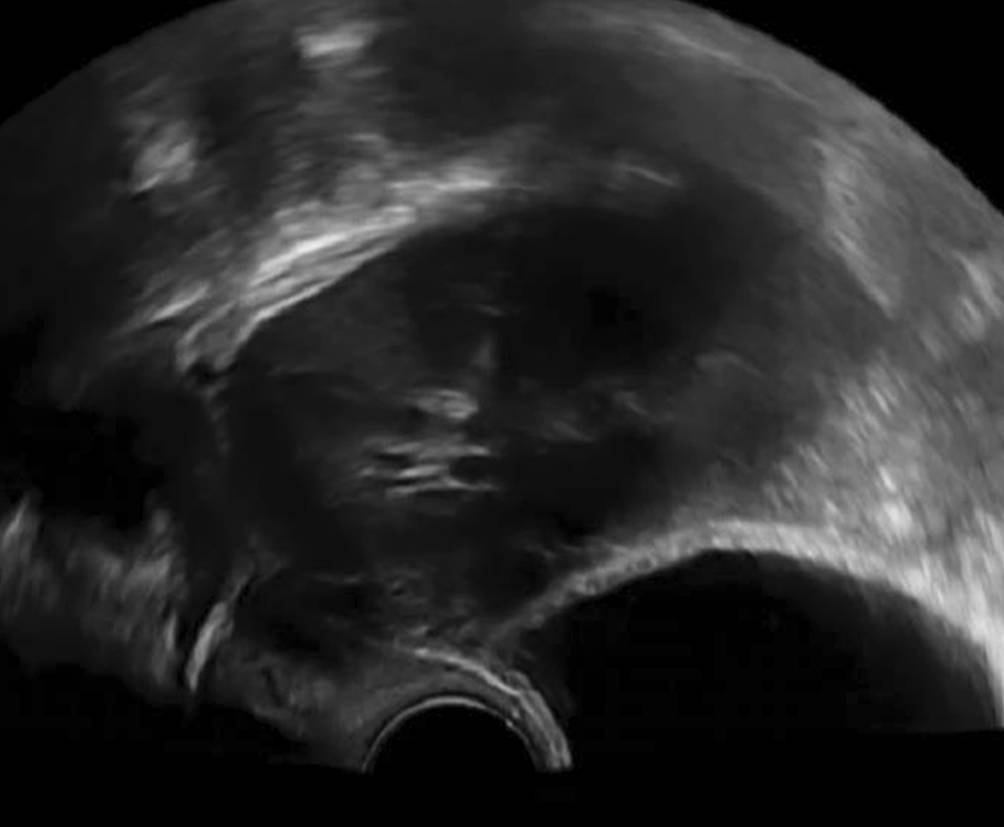

Die Gartner-Gang-Zyste

Gartner-Gang-Zysten sind im Prinzip harmlos, das Innere der Zysten ist meist dünnflüssig, kann aber auch gallertartige Konsistenz haben [4]. Selten – und dann eher im jugendlichen Alter – können sie sehr groß werden [5]. Es gibt einzelne Fallberichte von malignen Prozessen im Vaginalbereich, die aus Gartner-Gang-Zysten entstanden sein sollen [6, 7]. Beobachten mittels Bildgebung ist bei symptomlosen Patientinnen einer Punktion oder Exzision auf jeden Fall vorzuziehen (Abb. 5 und 6).

Abb. 5

Mit dem Abdominalschallkopf von perineal geschallte, seit 4 Jahren konstante Gartner-Gang-Zyste im Bereich des Fornix vaginae

Abb. 6

Über Jahre konstante Gartner-Gang-Zyste, die trotz der unmittelbaren Nähe zur Blase der Patientin nie Beschwerden machte